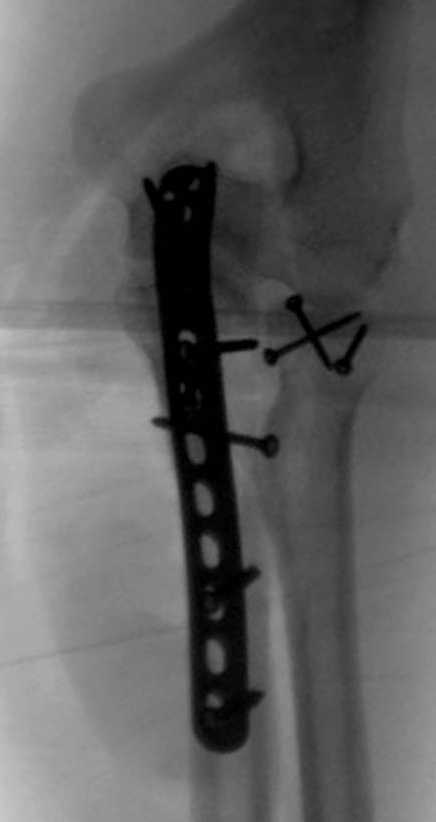

Здесь выставлены несколько случаев и варианты фиксации локтевого отростка, некоторые в комбинации с другими переломами.

2 вариант

перелом локтевого отростка с переломом головки лучевой кости (использованы 2 мм шурупы)